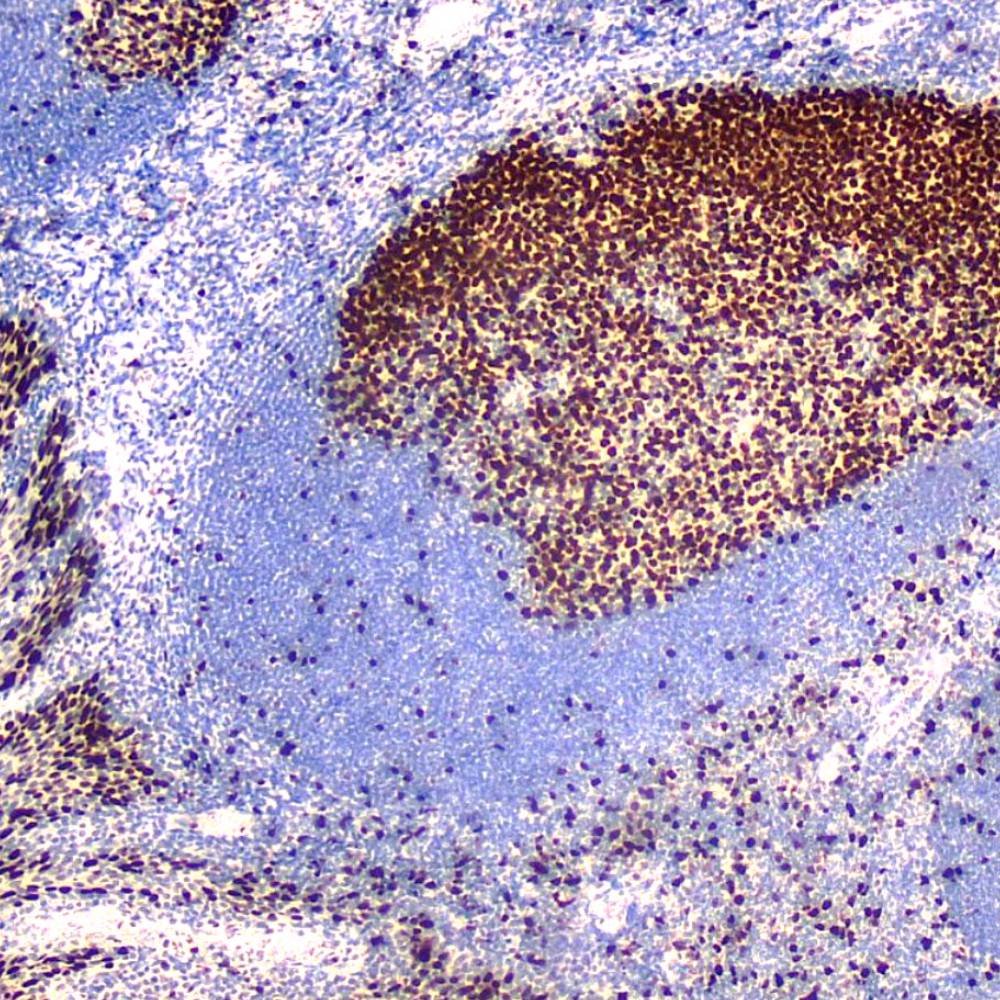

The Ki-67 protein is a nuclear protein doublet, 345-395 kDa, playing a pivotal role in maintaining cell proliferation. In diagnostic histopathology and cell biology, the antibody has proven valuable for the demonstration of the Ki-67 antigen in normal and neoplastic cells, for example in soft-tissue sarcoma, prostatic adenocarcinoma, and breast carcinoma. The Ki-67 has been confirmed as a very powerful single prognostic factor for overall survival, with highly proliferative cases showing a much poorer outcome than tumors with low proliferation. In breast cancer, the proliferative index measured by Ki-67 immunoreactivity has both prognostic and predictive value.